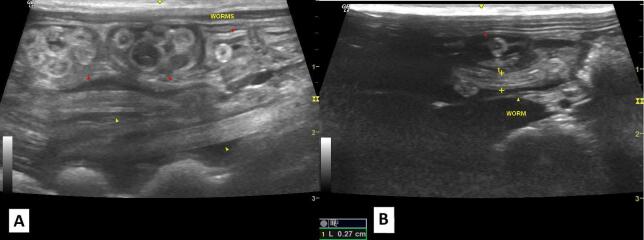

类蚓蛔虫感染是一项重大的全球卫生挑战,影响人类和非人类灵长类动物。在非人灵长类动物中,类蚓蚓感染对保护工作构成重大威胁,因为它们可以影响圈养种群和野生种群,引起从轻微到严重的并发症。本研究报告了在动物园饲养的两只黑sakis (Chiroptes uttahickae),一只雄性和一只雌性,由于体重减轻而进行常规检查。超声检查显示肠内有大量大蛔虫。雌鼠给予吡喃吡酯治疗,雄鼠给予芬苯达唑治疗,均取得成功。这些蠕虫被送去进行形态学和分子鉴定,并提交给新的检查。这一病例强调了在动物园进行预防性兽医检查的重要性,特别是对构成人畜共患病风险的寄生虫进行检查,以确保动物和人类健康。

Ascaris lumbricoides infections represent a major global health challenge, affecting both humans and non-human primates. In non-human primates, A. lumbricoides infections pose a significant threat to conservation efforts, as they can impact both captive and wild populations, causing complications ranging from mild to severe. This study reports the case of two black sakis (Chiroptes utahickae) kept under human care in a zoo-a male and a female-presented for routine examination due to weight loss. Ultrasonography revealed a substantial intestinal infestation of large roundworms. The female was treated with pyrantel pamoate, and the male with fenbendazole, both with successful outcomes. The worms were sent for morphological and molecular identification, and the animals were submitted for new examinations. This case underscores the importance of preventive veterinary check-ups in zoos, particularly for parasites that pose zoonotic risks, to ensure both animal and human health.